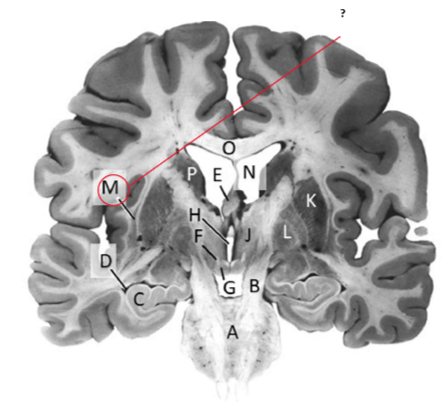

Name this and state its function.

Corpus Callosum.

Name and state its function.

Lateral ventricles.

Hippocampus.

Thalamus.

Third ventricle.

Caudate nucleus.

Name this ,state its function and the name of the structures closely associated with it.

Putamen.

Name this, state its function and its components[4 marks].

Globus Pallidus.

Components:

Crus Cerebri.

Name this and state its function. Also, state all 3 fibres involved.

Basilar pons.

Claustrum.

Name.

Temporal horn of lateral ventricle.

Name this, state its function and consequence of lesion in this area.

Fornix.

Transmits Theta waves aswell.

Lesion: anterograde amnesia.

Name this and state its function. And what tract is involved?

Mamillary bodies.